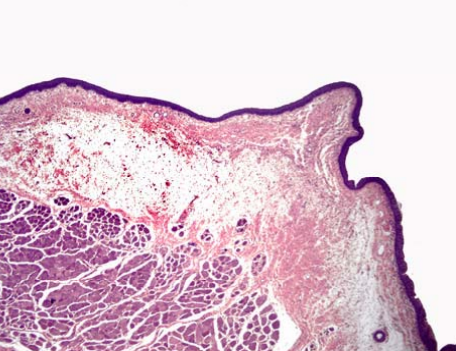

how do you know this is a vocal cord portion of larynx?

what type of region of the larynx is this? how do you know?

transitional.

the epithelium transitions from respiratory to stratified squamous epithelium.

vocal cord

no serous glands

and squamous stratified epithelium